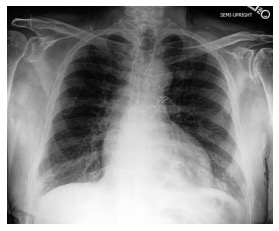

Automated diagnosis prediction from medical images is a valuable resource to support clinical decision-making. However, such systems usually need to be trained on large amounts of annotated data, which often is scarce in the medical domain. Zero-shot methods address this challenge by allowing a flexible adaption to new settings with different clinical findings without relying on labeled data. Further, to integrate automated diagnosis in the clinical workflow, methods should be transparent and explainable, increasing medical professionals' trust and facilitating correctness verification. In this work, we introduce Xplainer, a novel framework for explainable zero-shot diagnosis in the clinical setting. Xplainer adapts the classification-by-description approach of contrastive vision-language models to the multi-label medical diagnosis task. Specifically, instead of directly predicting a diagnosis, we prompt the model to classify the existence of descriptive observations, which a radiologist would look for on an X-Ray scan, and use the descriptor probabilities to estimate the likelihood of a diagnosis. Our model is explainable by design, as the final diagnosis prediction is directly based on the prediction of the underlying descriptors. We evaluate Xplainer on two chest X-ray datasets, CheXpert and ChestX-ray14, and demonstrate its effectiveness in improving the performance and explainability of zero-shot diagnosis. Our results suggest that Xplainer provides a more detailed understanding of the decision-making process and can be a valuable tool for clinical diagnosis.